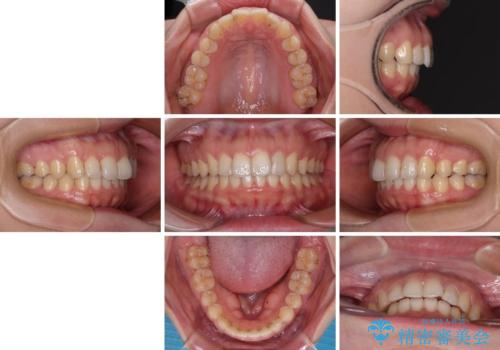

インビザライン矯正で前歯のデコボコを改善

- 前歯のデコボコを気にして来院された患者様です。

目立たないことを最優先にしたいとのことで、デコボコは軽度であったことから、インビザラインにて矯正治療を行うこととしました。

骨格的に下顎骨が左にずれており、上下の正中一致は困難ではありましたが、IPR(歯と歯の間を削る)や後方への移動など組み合わせて、できる限り改善しました。

インビザラインはマウスピースを外している時間が長いと、長期間使用しても前歯のデコボコはあまり改善されません。こちらの患者様は治療期間が長くなり、装着時間が短くなってしまったことで、気になる部分の改善により長期間を要するようになってしまいました。